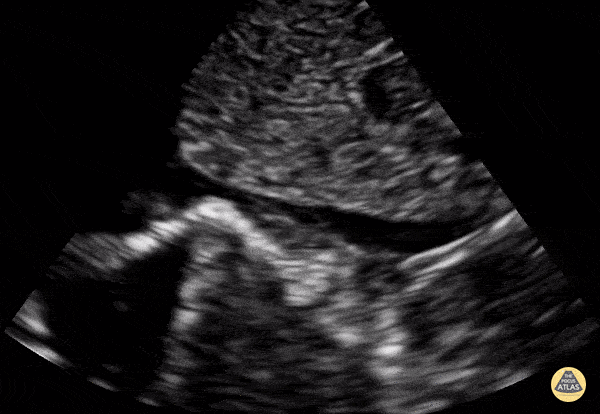

Normal Toddler IVC. Contributor: Jaron Smith, MD, Phoenix Children's Hospital

View: Unspecified Parasternal Long Axis Parasternal Short Axis Apical Four-Chamber Subcostal Four-Chamber Subcostal Inferior Vena Cava Right Upper Quadrant Left Upper Quadrant Suprapubic Longitudinal Suprapubic Transverse Subxiphoid Anterior Thoracic Phrenic